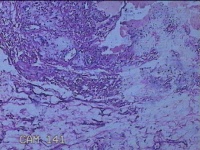

右手掌肿物

性别

女

年龄

32岁

临床诊断

1.右手掌肿物性质待查?右腕管综合征

一般病史

发现右手掌肿物疼痛伴拇示中指感觉迟钝约6年。

标本名称

大体所见

灰白粉红色肿物2.5x2x0.8cm一个,表面光滑,切开肿物呈实性,切面灰白粉红色,质软。